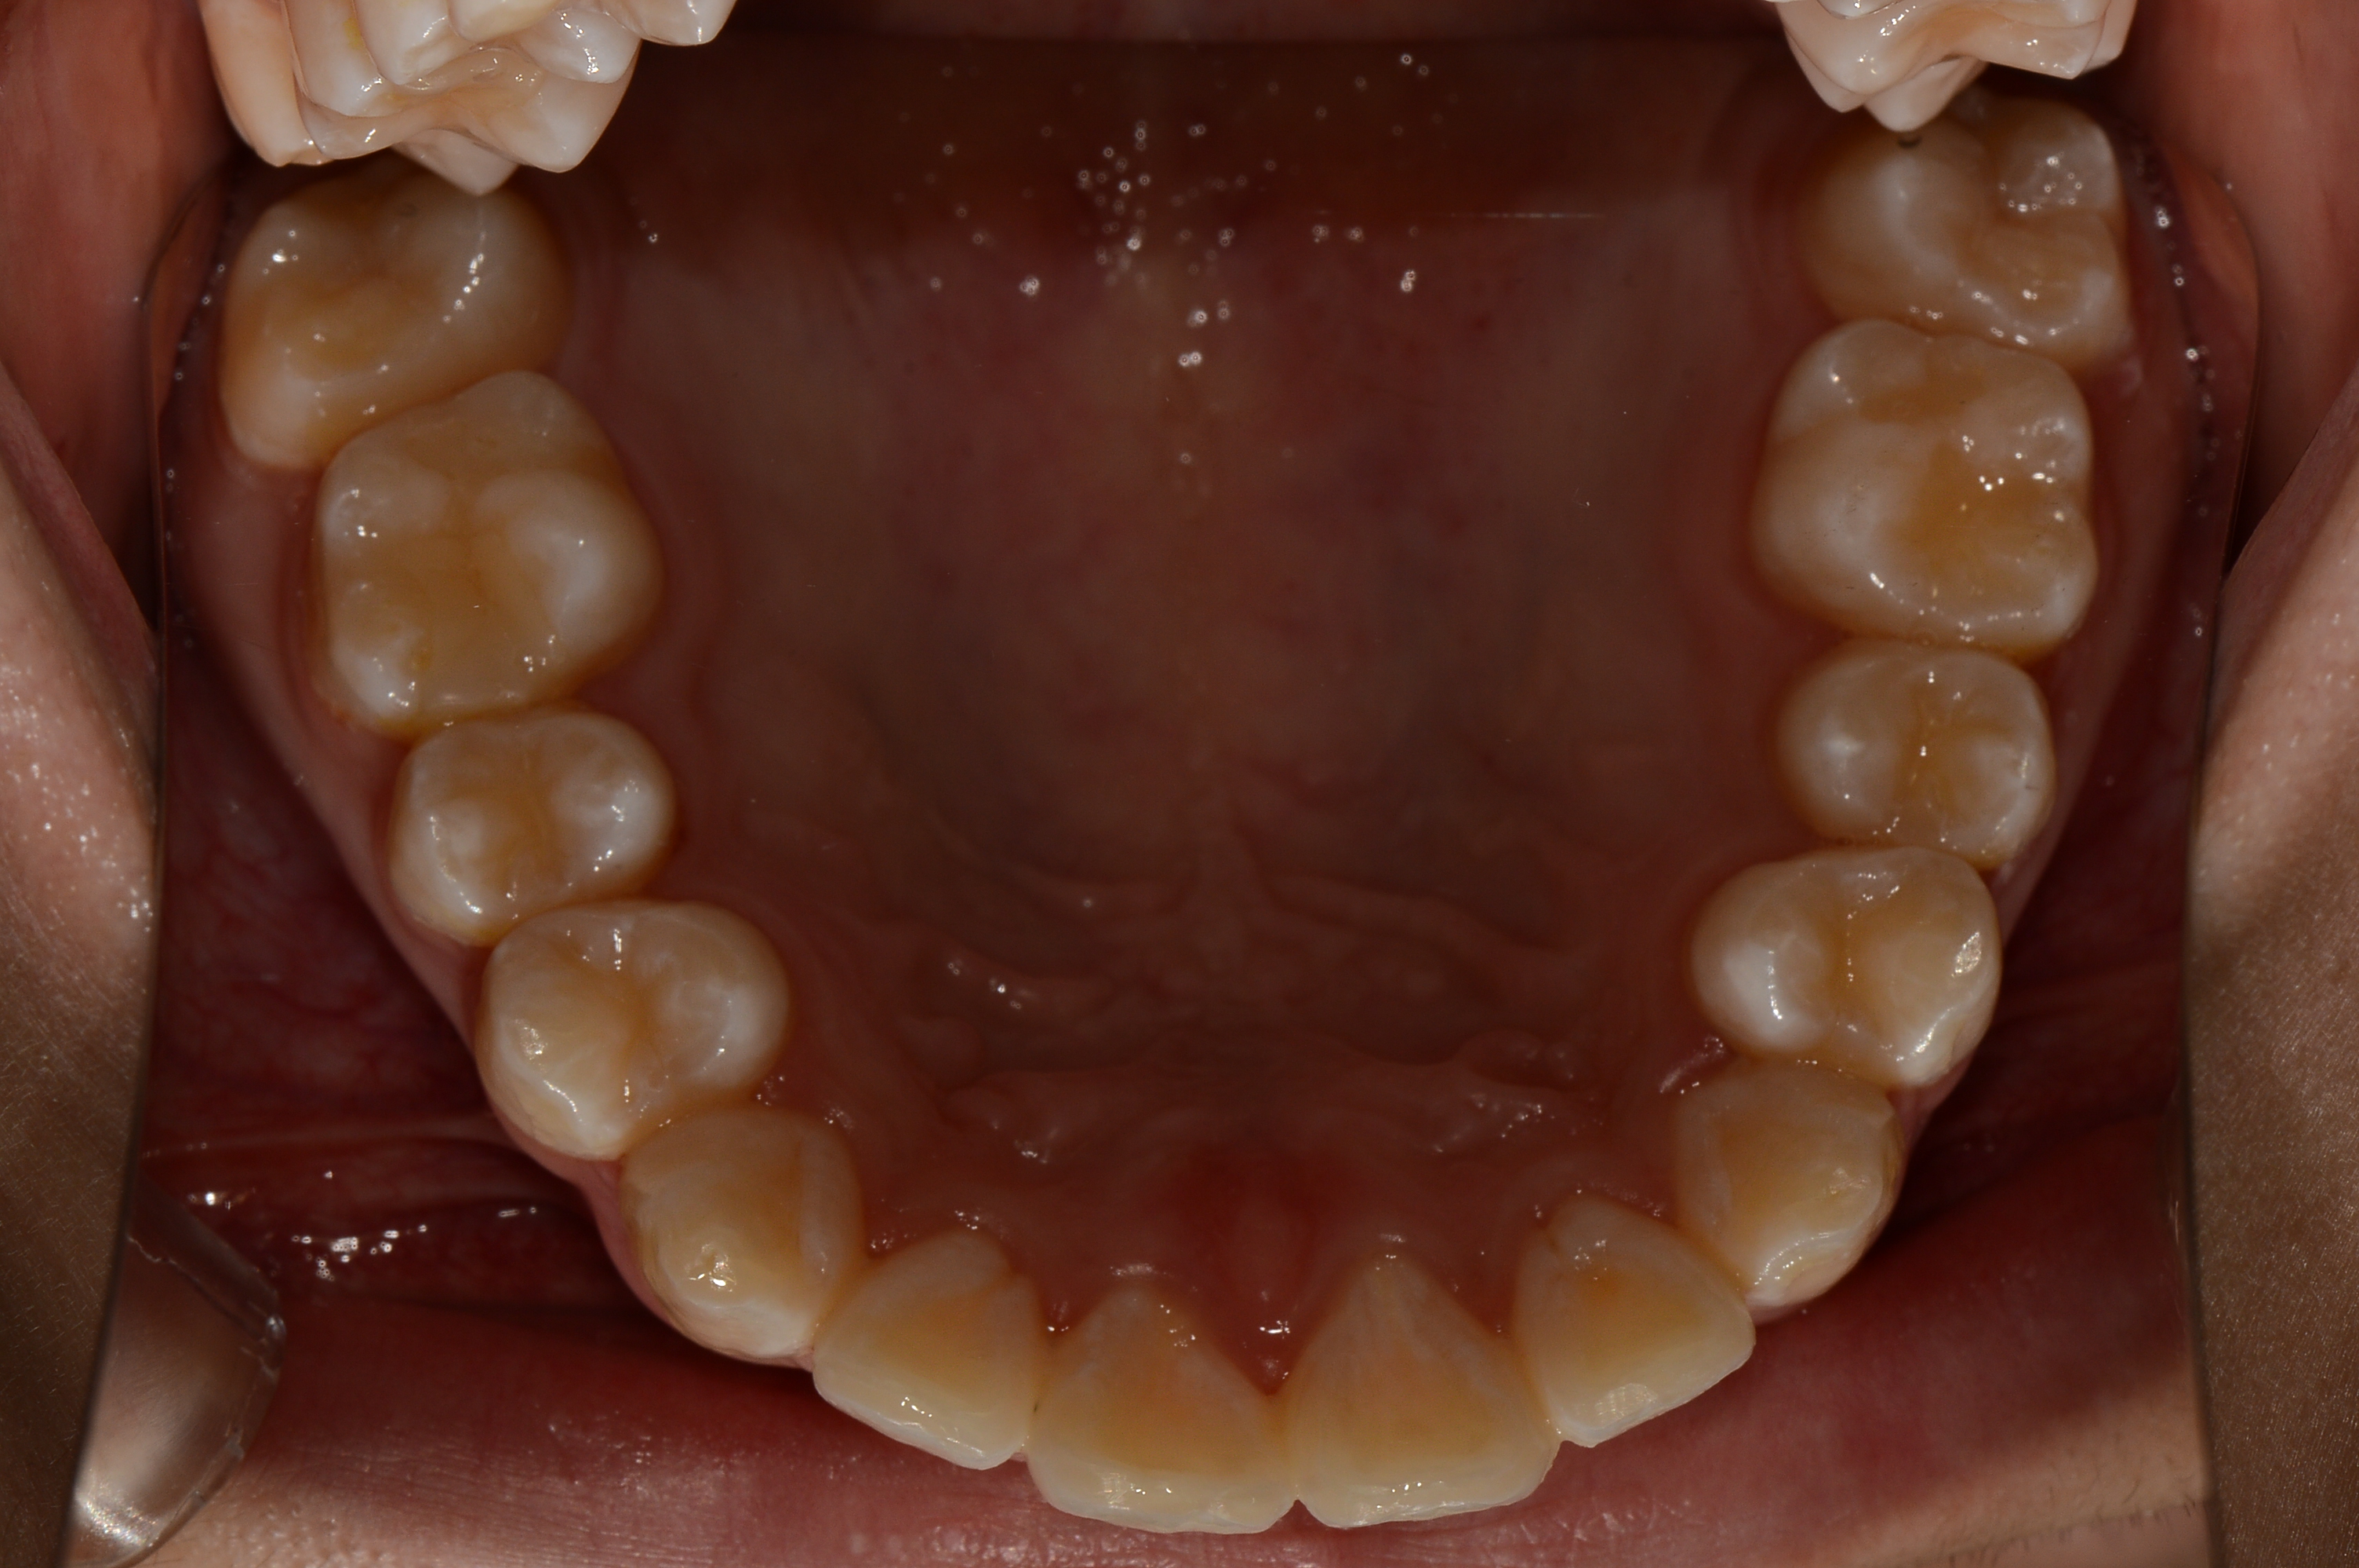

치료 전 사진입니다.